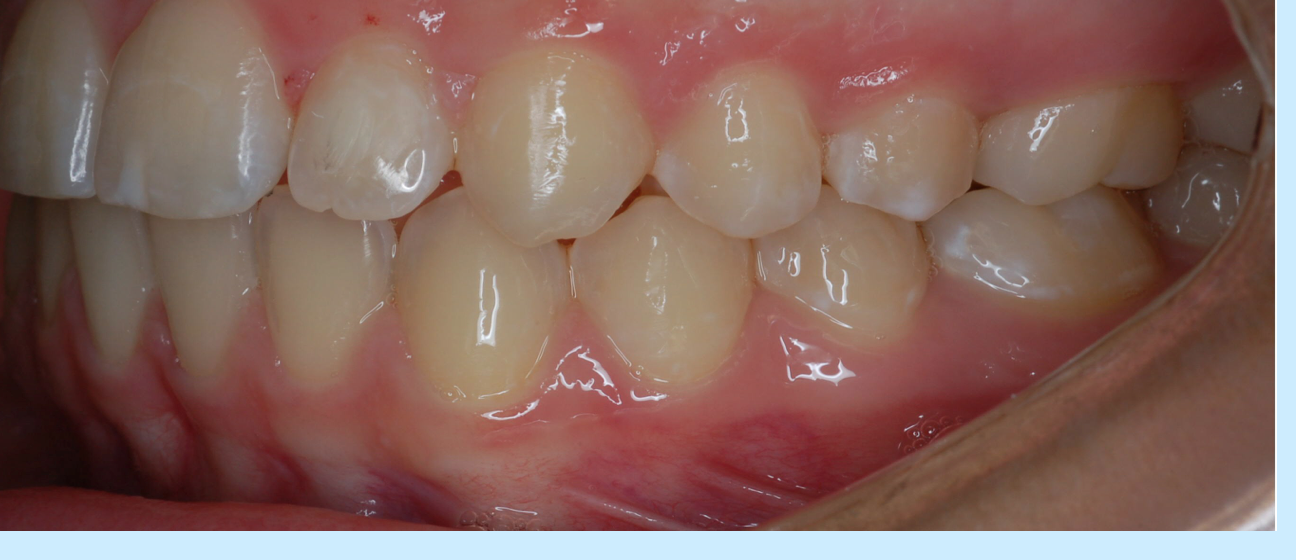

1-class 1

2-class 1 malocclusion

3-class 2 malocclusion

4-class 2 division 1

5-class 2 division 2

6-subdivision

1-upper 1st molars are key to occlusion

mesio-buccal cusp of upper first molar occludes in buccal grove of lower first molar

2-normal relationship of molars, line of occlusion= incorrect bc of malposed teeth, rotations, etc.

3-lower molar positioned distally relative to upper molar, line of occlusion isnt specified

4-large overjet

5-normal overjet

6-molars are class 2 on one side only